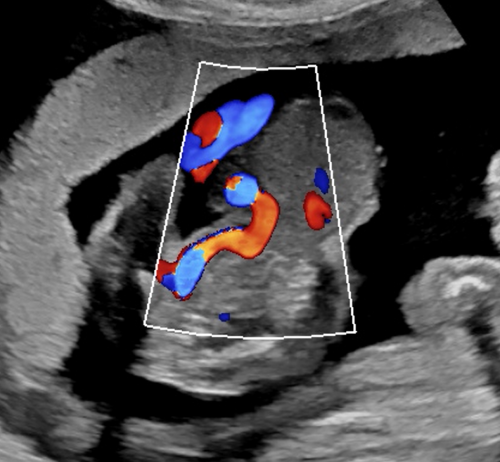

Sonoanatomie, Biometrie, Hinweiszeichen & Diagnose von Entwicklungsstörungen, Kasuistiken, ausreichend Zeit für Diskussionen, Fallbeispiele aus der Praxis (Quiz)